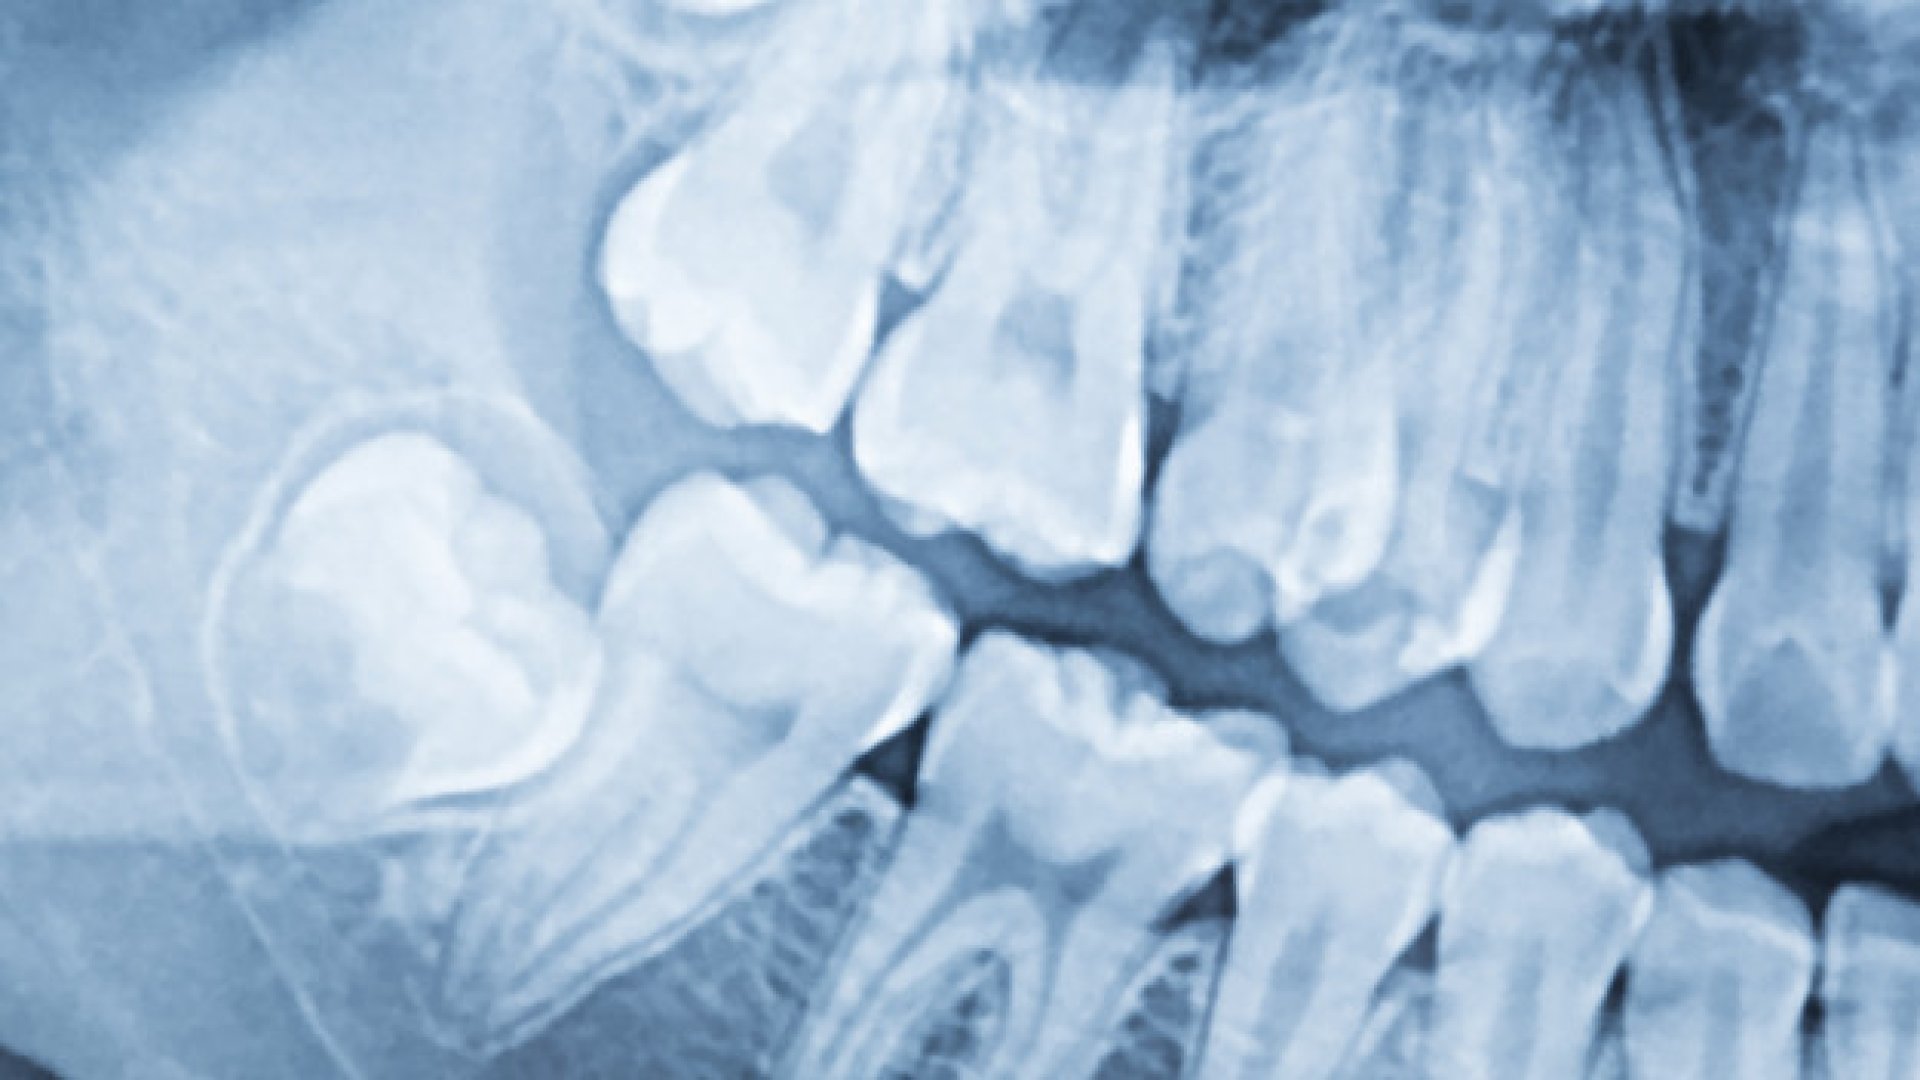

Digitális panoráma röntgen vagy CBCT segítségével. Nyugodt környezetben átbeszéljük a műtét menetét és megválaszoljuk kérdéseit.